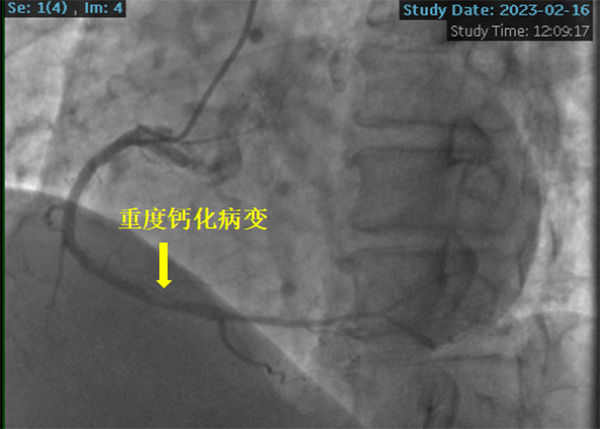

患者冠脈造影提示右冠狀動(dòng)脈重度鈣化病變,狹窄程度達(dá)到90%-95%,左主干及左前降支彌漫鈣化伴中重度狹窄。潘德鋒主任團(tuán)隊(duì)與心臟大血管外科王國(guó)祥主任團(tuán)隊(duì)會(huì)診討論后,與患者家屬充分溝通病情,考慮到患者急性心梗、腦病等因素,決定采用冠脈支架植入術(shù)治療罪犯病變-右冠狀動(dòng)脈重度鈣化病變。

冠脈鈣化病變被稱為“最硬的骨頭”或“最堅(jiān)硬的堡壘”, 可導(dǎo)致介入器械難以通過(guò)或不能通過(guò)病變,即刻成功率低,并發(fā)癥發(fā)生率高等嚴(yán)重后果。針對(duì)患者病情及冠脈病變的復(fù)雜性,潘德鋒主任決定采用被譽(yù)為“拆彈專家”的沖擊波球囊技術(shù)治療冠脈嚴(yán)重鈣化病變。